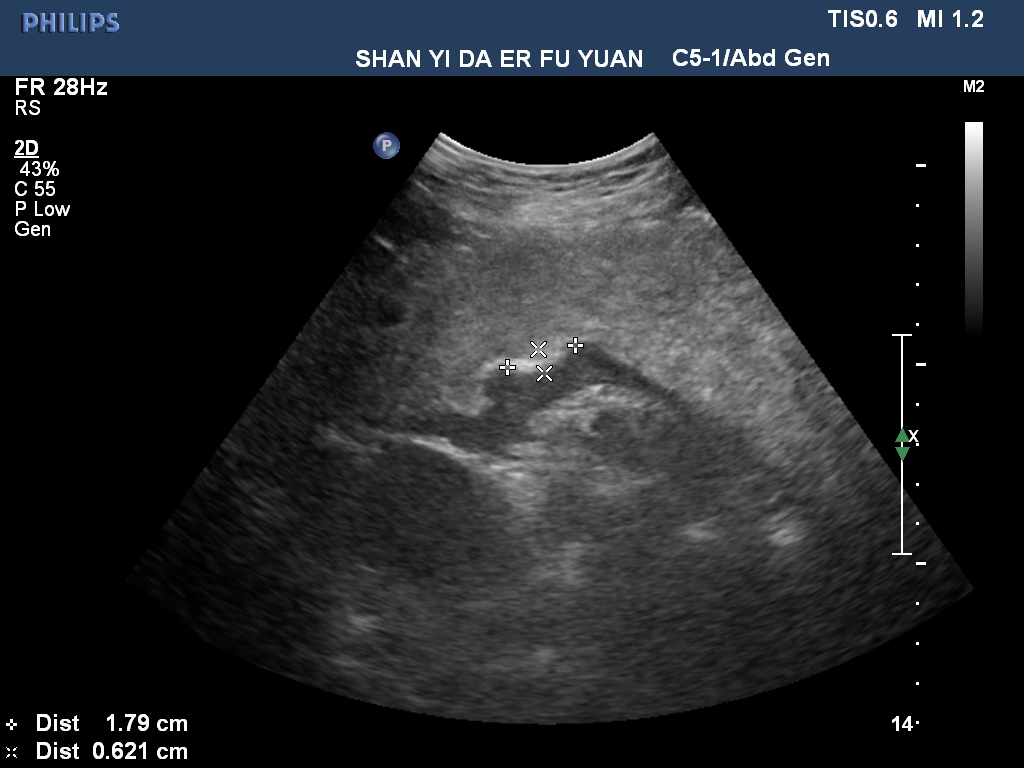

胃潰瘍